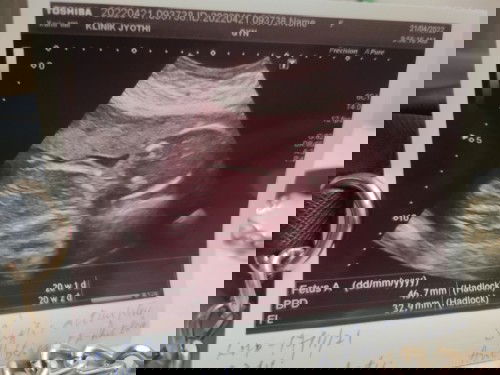

Betul ke boy?

Betul ke boy? Tadi saya scan jantina di klinik. Swasta.. Anak no 2ni teruja sikit sbb yg first boy..memang Mngharap second ni girl la.. Yg first tak pernah scan kat luar sbb tak kesah anak pertama lelaki ke perempuan.. Nak tanya kadang boleh jadi silap ke scan di swasta. .tp td jelas doc tunjuk bird2 dia. .mana la tahu silap ke. .🤭